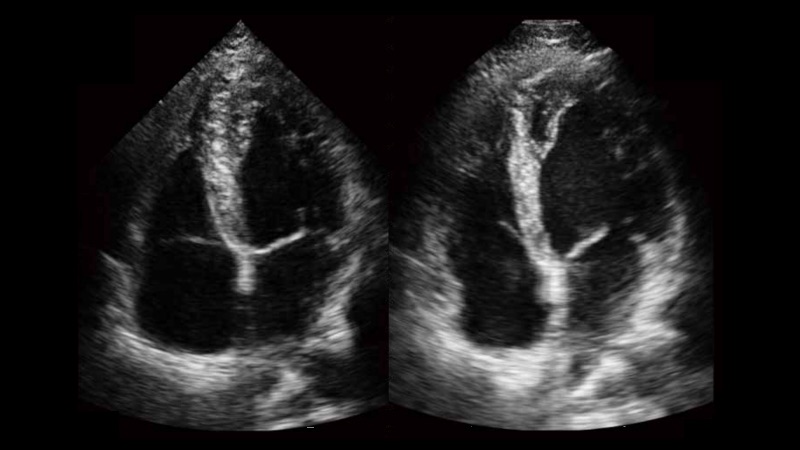

自动识别收缩和舒张末期心肌内膜,自动计算射血分数EF值。